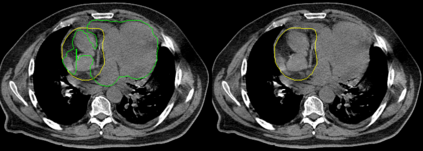

Organ-at-risk contouring is still a bottleneck in radiotherapy, with many deep learning methods falling short of promised results when evaluated on clinical data. We investigate the accuracy and time-savings resulting from the use of an interactive-machine-learning method for an organ-at-risk contouring task. We compare the method to the Eclipse contouring software and find strong agreement with manual delineations, with a dice score of 0.95. The annotations created using corrective-annotation also take less time to create as more images are annotated, resulting in substantial time savings compared to manual methods, with hearts that take 2 minutes and 2 seconds to delineate on average, after 923 images have been delineated, compared to 7 minutes and 1 seconds when delineating manually. Our experiment demonstrates that interactive-machine-learning with corrective-annotation provides a fast and accessible way for non computer-scientists to train deep-learning models to segment their own structures of interest as part of routine clinical workflows. Source code is available at \href{https://github.com/Abe404/RootPainter3D}{this HTTPS URL}.